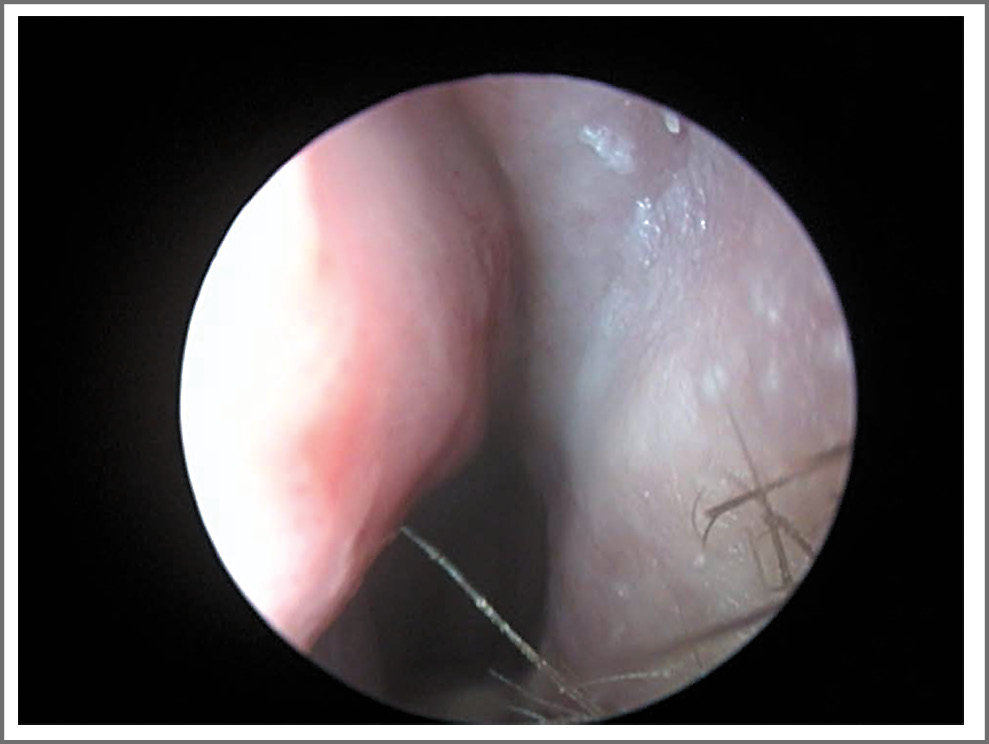

Локальный статус: форма наружного носа не изменена. Область проекции околоносовых пазух визуально не изменена, безболезненна при пальпации и перкуссии. Слизистая носа гиперемирована, пастозна, слизистое отделяемое в носовых ходах. В области перегородки носа с 2 сторон имеется гиперемированный инфильтрат с признаками флуктуации (рис. 3). Носовое дыхание резко затруднено. Полость носа не обозрима.

Рис. 3. Абсцесс перегородки носа.

С целью санации гнойного очага произведено вскрытие абсцесса перегородки носа, получено гнойное отделяемое 4 мл, установлен резиновый дренаж, тампонада носа с 2 сторон турундой с мазью Левомеколь. Проводилась антибактериальная терапия (цефотаксим + метронидазол).